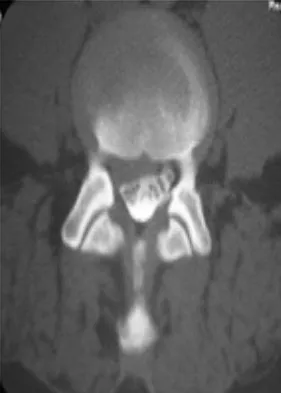

An 18-month-old boy with obstetric brachial plexus palsy is being evaluated for limited right shoulder motion. Physical therapy for the past 6 months has failed to result in improvement of the contracture. Which of the following studies is necessary prior to any shoulder reconstruction?